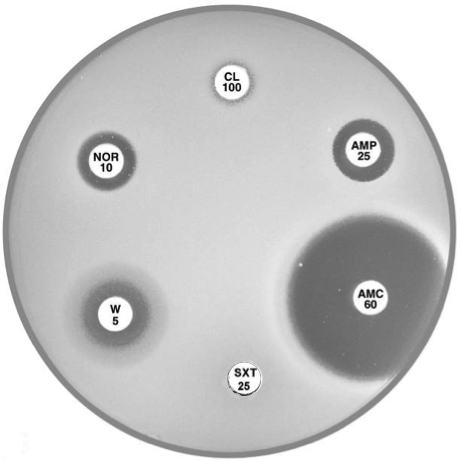

Plate 12.6.A Acinetobacter lwoffi A large inhibitory zone around ampicillin (AMP 25), a smaller one around cephalexin (CL 100), resistance to trimethoprim (W 5) and a lack of synergy with sulphonamide (SXT 25) are typical of A. lwoffi |

Plate 12.6.B Acinetobacter baumannii Note the large inhibitory zone around amoxycillin-clavulanic acid (AMC 60), a small one around ampicillin (AMP 25) and none around cephalexin (CL 100). |